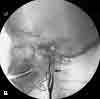

Figure 1

The initial CT scan of the brainshowed a linear hyperdensity in theregion of the left middle cerebral artery,which indicated thrombus formation(Figure 1). An area of cerebral edemawas noted in the region with a smalleffacement from left to right. A cerebralangiogram performed 6 hours after theCT scan revealed a complete dissectionof the left internal carotid artery (ICA)from the second cervical segmentcraniad (Figure 2). A follow-up CTbrain scan 24 hours later demonstrateda large, left middle cerebral arteryischemic infarction with midline shiftingand evidence of left uncal herniation(Figure 3).